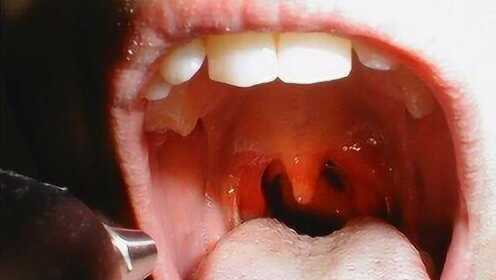

慢性咽炎是一種常見(jiàn)的喉部疾病,主要表現(xiàn)為咽部不適、干燥、瘙癢、疼痛等癥狀,由于長(zhǎng)期受到刺激或感染,咽部黏膜出現(xiàn)慢性炎癥表現(xiàn),慢性咽炎雖然不是嚴(yán)重疾病,但癥狀反復(fù)發(fā)作,嚴(yán)重影響患者的生活質(zhì)量。